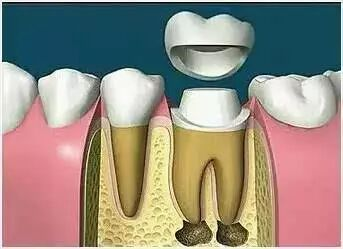

六、根管治疗后为什么还需要做全冠保护

很多病人不理解,为什么在根管治疗后,牙齿不疼了,补上就可以了,为什么还要做全冠保护,觉得没有必要。

事实上在根管治疗后,没有牙髓提供营养的牙齿会变暗、变脆,剩余的牙冠部分很容易折断劈裂,导致牙齿使用寿命减少,因此根管治疗后需做全冠对其进行保护。